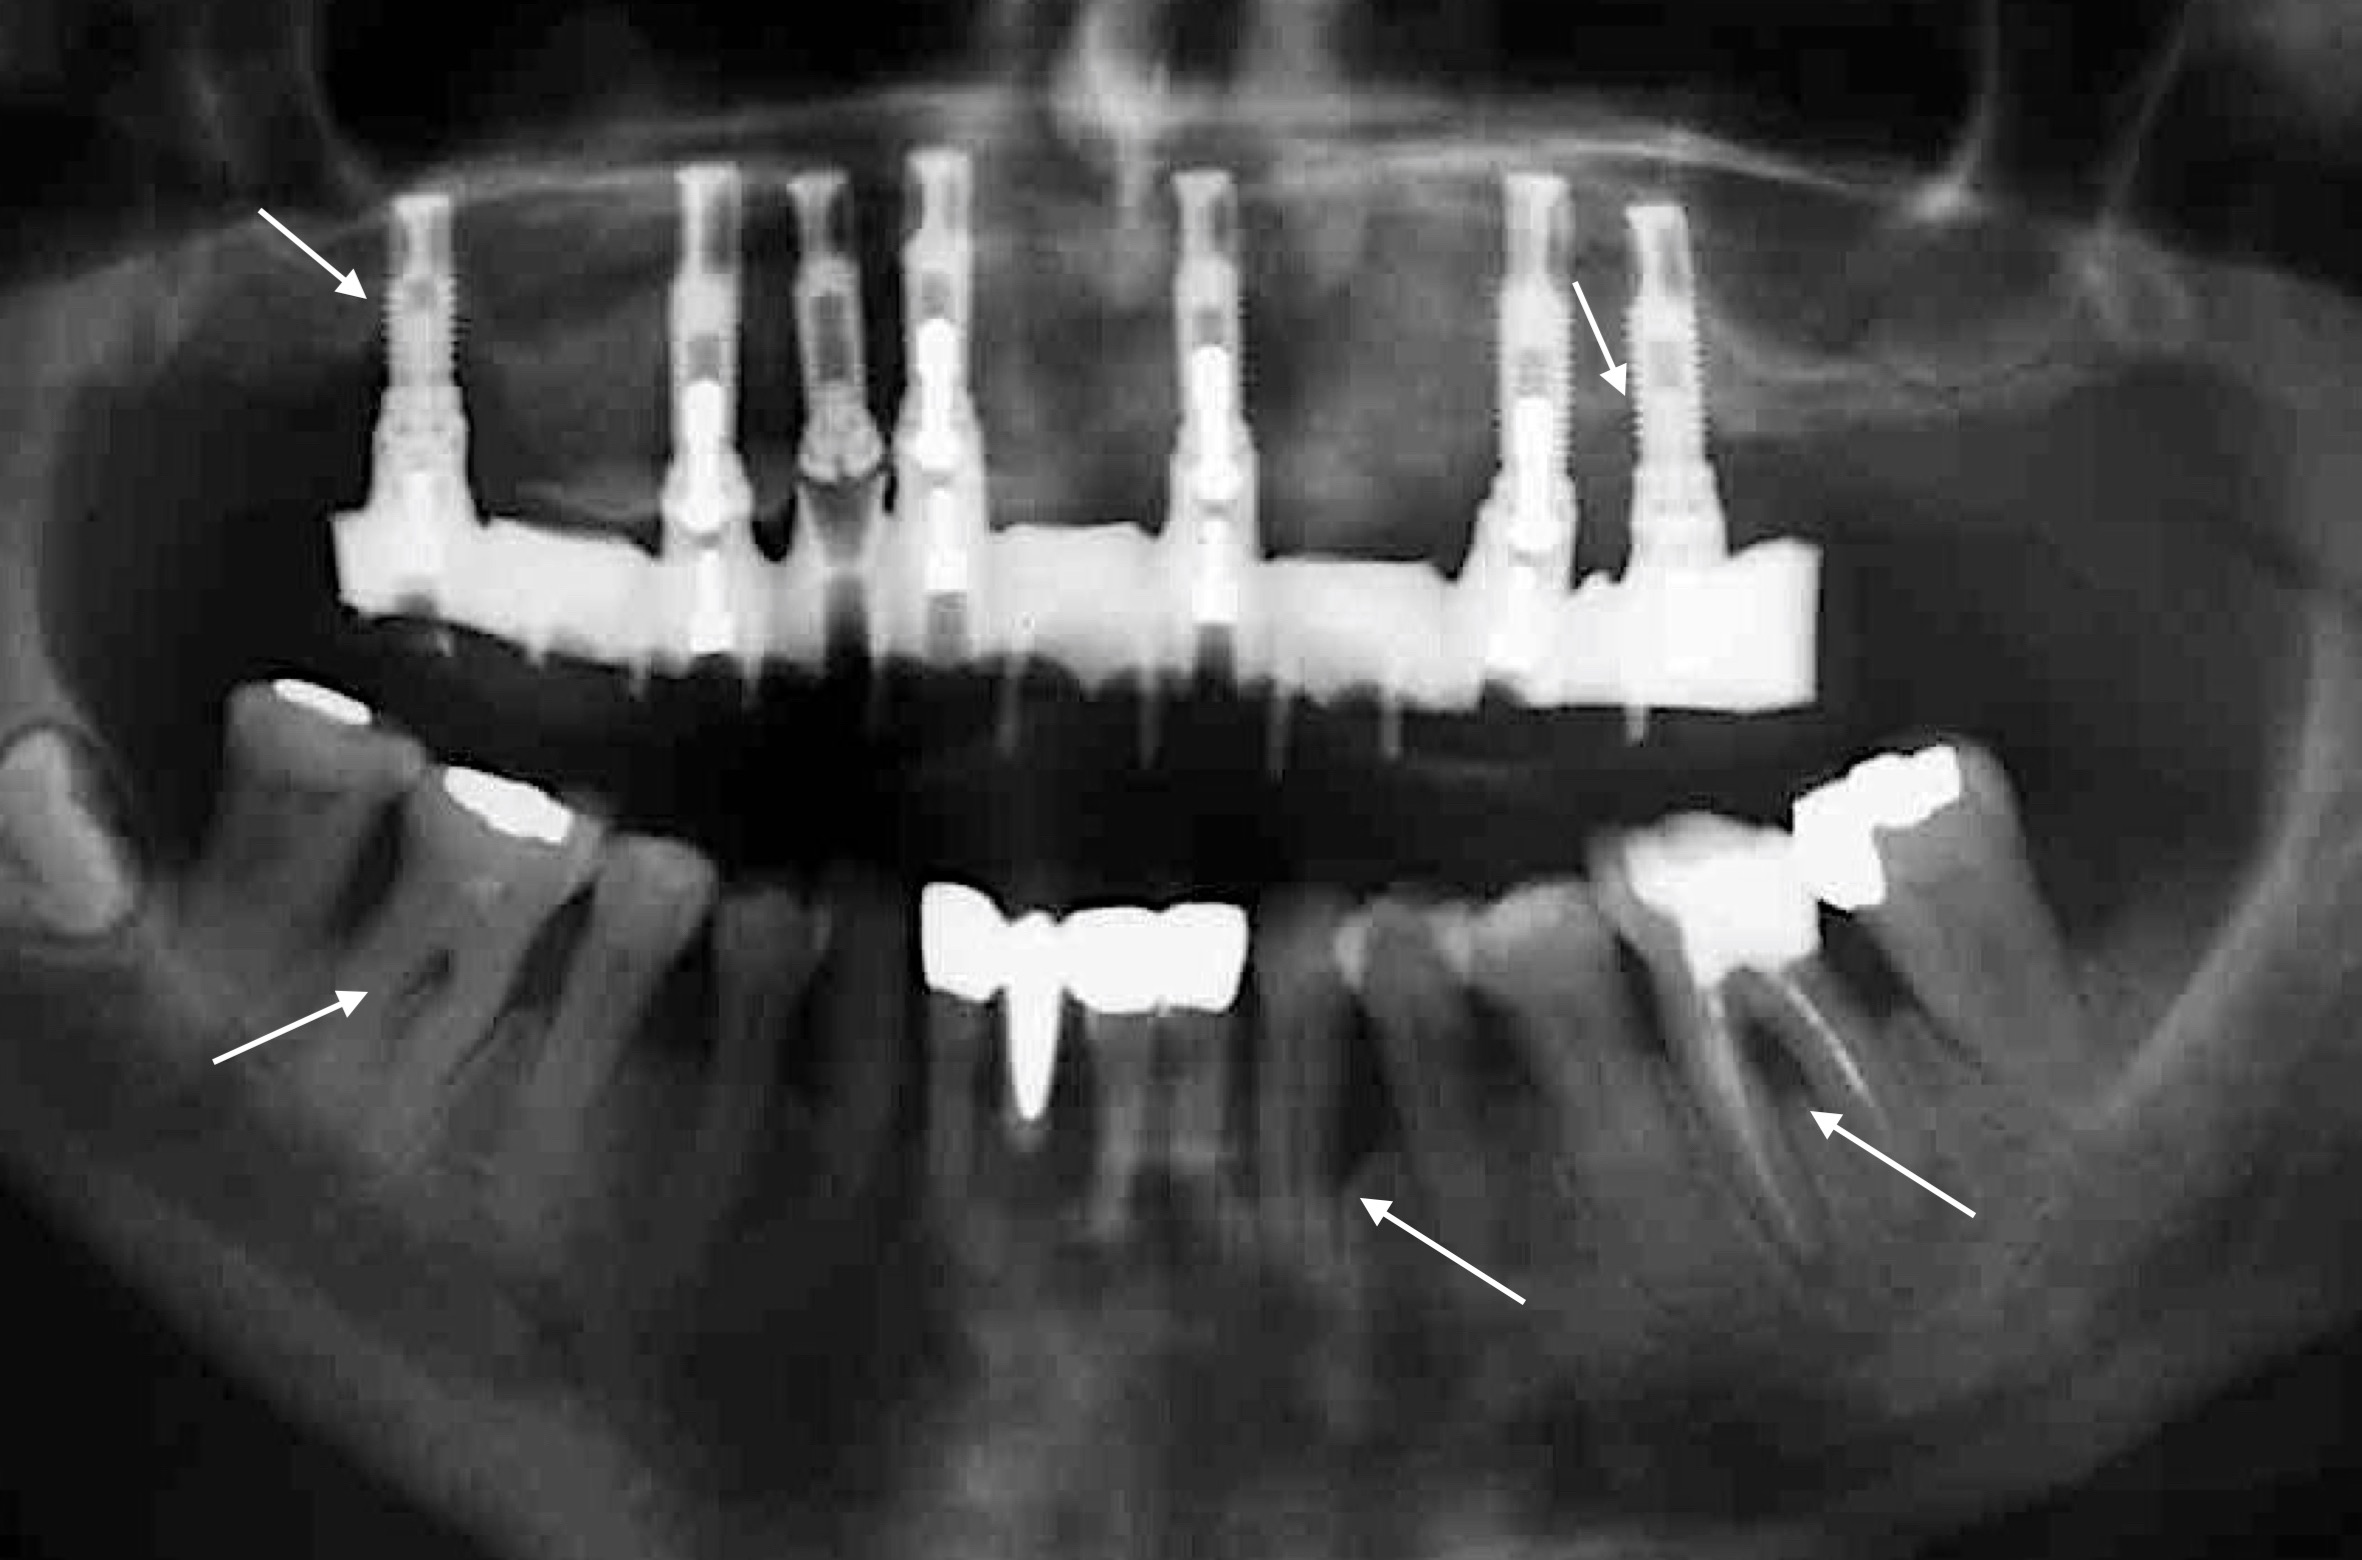

Numerous reviews from the last 10 years have shown that patients with underlying periodontal disease have a higher risk of implant failure (e.g. Renvert & Persson 2009, Sousa et al. 2016, and many others). In addition, this risk appears to be even higher among patients who have been diagnosed with generalized aggressive periodontitis (Monje et al. 2016). To avoid this complication wherever possible, the patient’s periodontal health must be maintained as strictly as possible. This means: 1) periodontal treatment must take place before implant treatment; 2) the patient’s oral hygiene must be rigorously optimized and, above all, the patient must be given precise new instructions after they have been fitted with their implant-retained prosthesis; 3) to prevent recurrence of the patient’s periodontitis and to enable early detection of peri-implant diseases, regular follow-up sessions must be scheduled and conducted; and 4) residual pocket probing depths should ideally be avoided after periodontal treatment! Why is the last point so important? A study from Australia (Cho-Yan Lee et al. 2012) showed very clearly that periodontitis patients with residual pocket probing depths (≥ 6 mm pocket probing depth) are at 4 to 5 times greater risk of developing peri-implantitis than periodontally healthy patients and periodontitis patients without residual pocket probing depths!